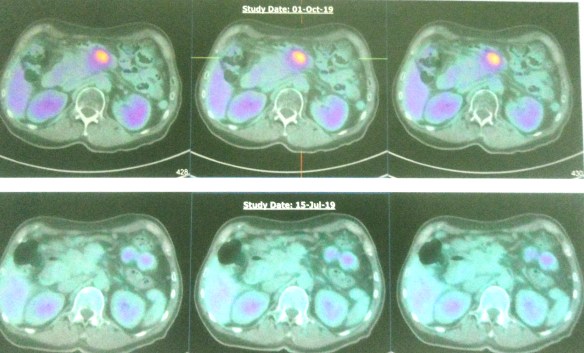

- PET scan on 14 September 2023 showed more serious condition.

- The metabolically active left lung mass with multiple neck, axillary and mediastinal nodes. Left pleura and bone lesions are likely due to primary lung malignancy.

- However, metastatic breast cancer recurrence cannot be excluded.